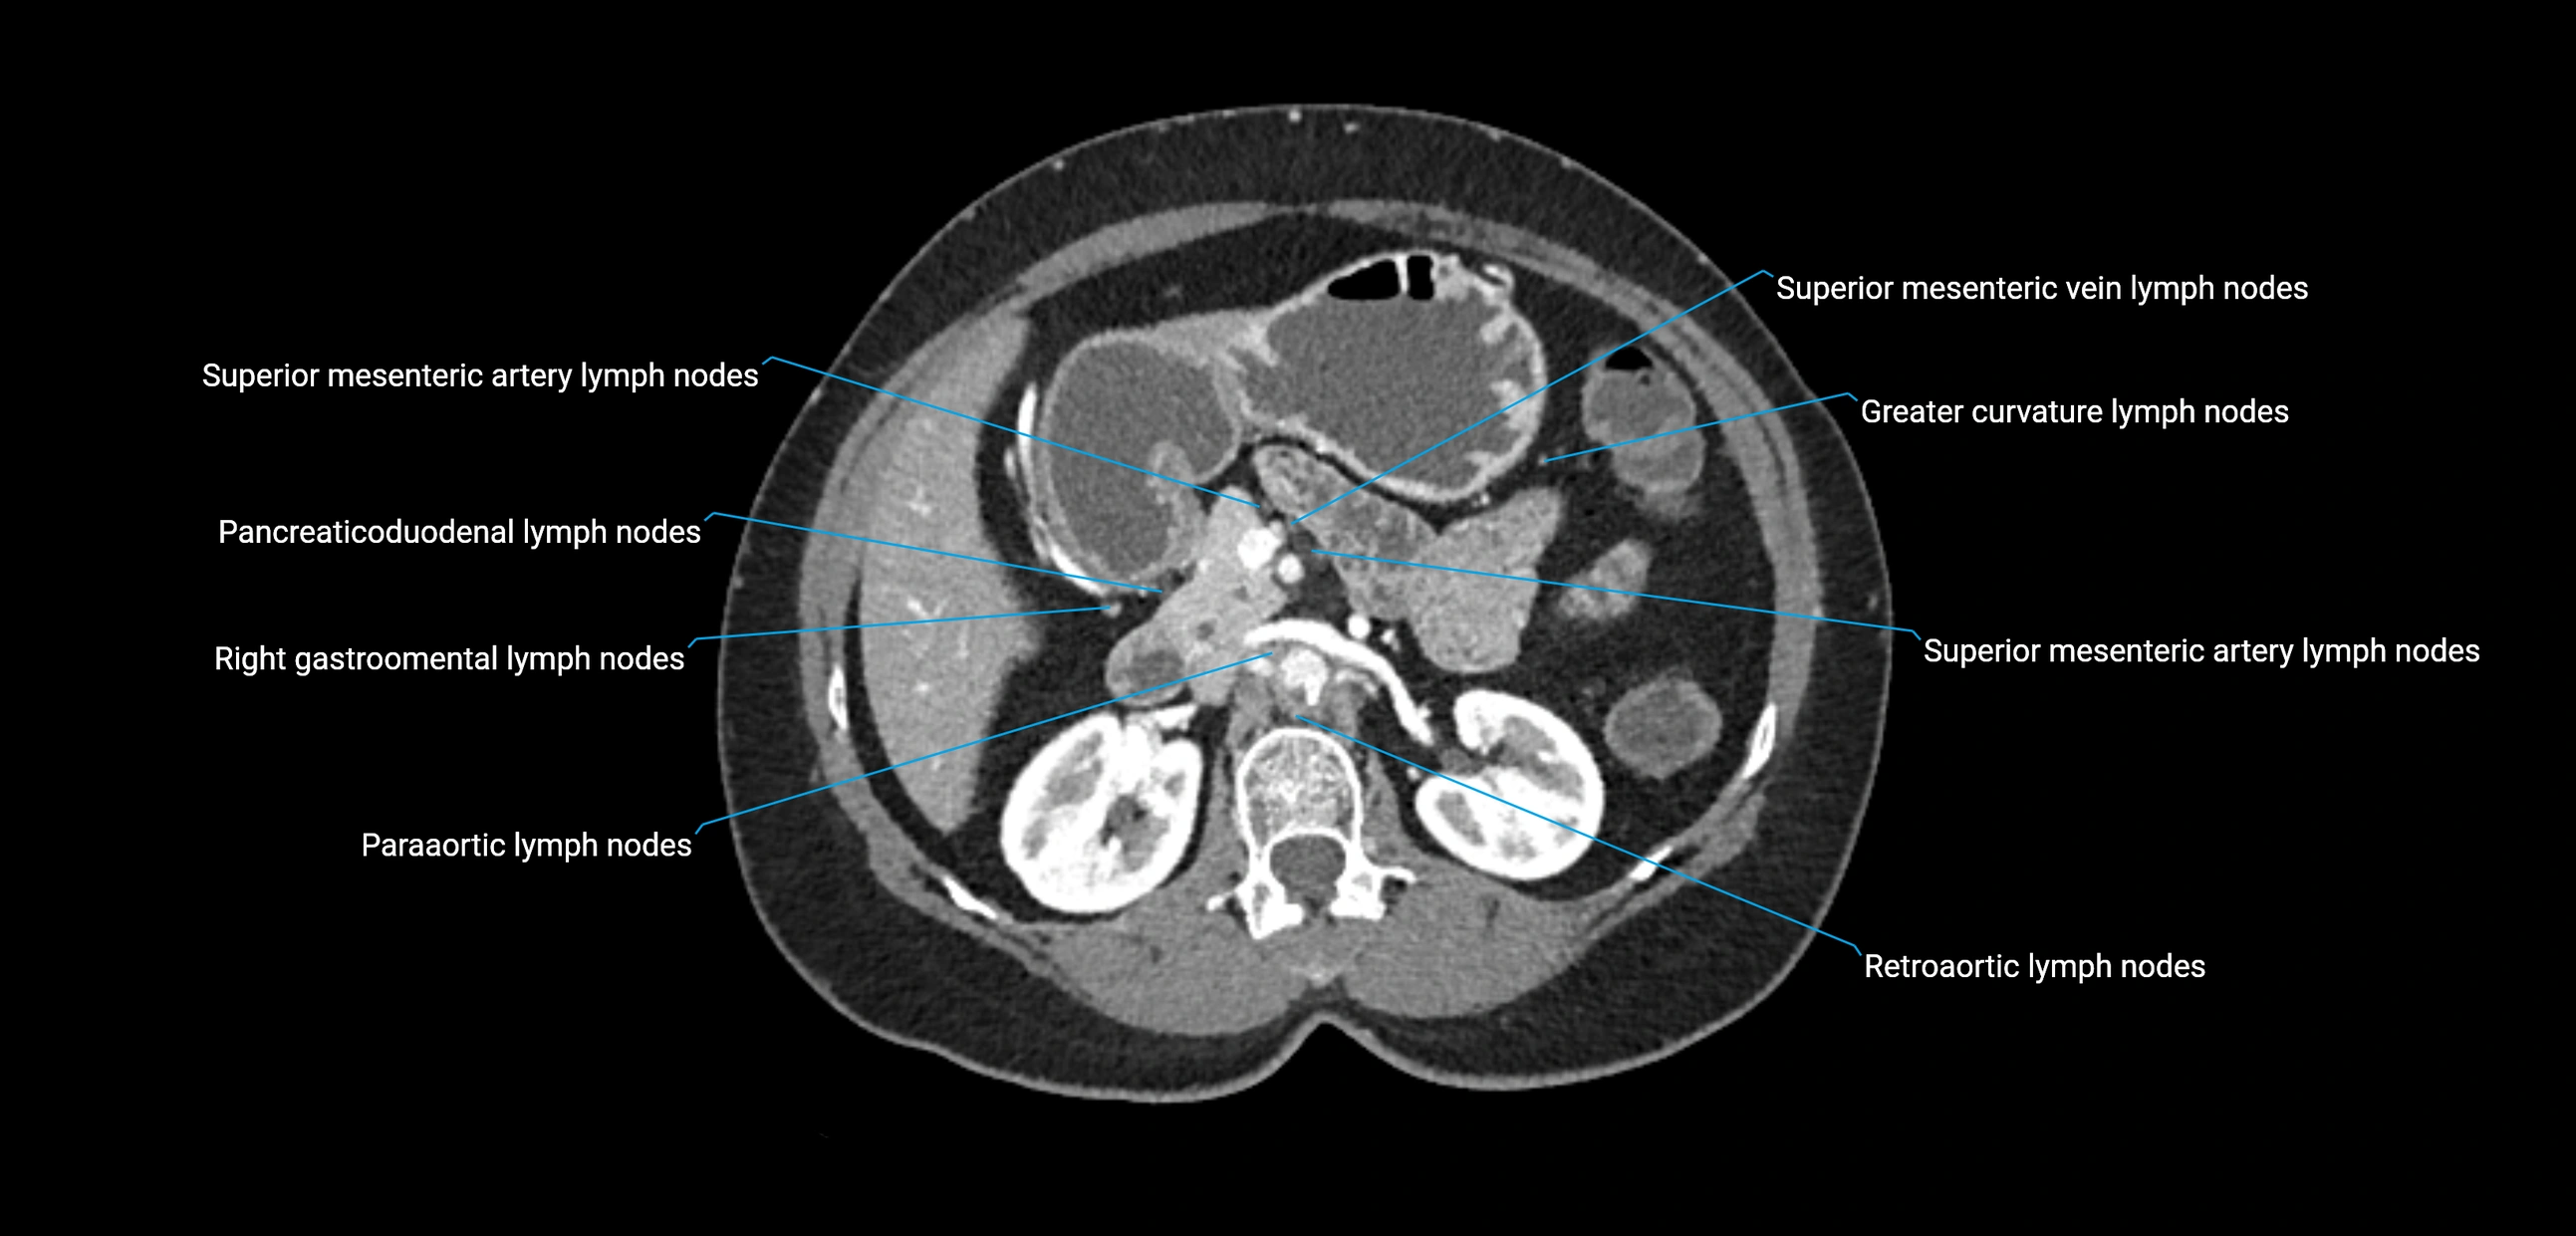

CT Appearance

CT Pre-Contrast:

• Nodes appear as soft-tissue density nodules adjacent to the aorta and IVC

• Calcification may be seen in chronic infections (e.g., tuberculosis)

CT Post-Contrast:

• Normal nodes enhance homogeneously

• Malignant nodes may show heterogeneous enhancement, central necrosis, or conglomerate formation

• Size >1 cm short axis is suspicious, though morphology and distribution are equally important

CT image

image